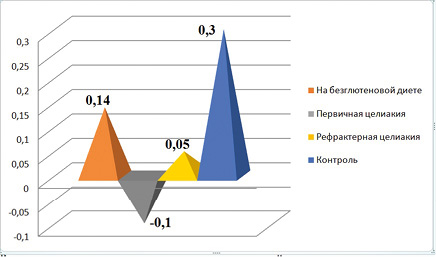

Цель исследования: определить клиническую значимость фекального кальпротектина при целиакии у детей, провести параллели между ФК и нарушением проницаемости тонкого кишечника.

Материалы и методы. В период с января 2018 г. по июнь 2019 г. обследовано 42 ребенка: 28 с впервые выявленной целиакией, 14 больных с ранее установленным диагнозом, соблюдавших аглютеновую диету, и 20 практически здоровых детей аналогичного возраста (контрольная группа). Всем детям проводилось определение антител к тканевой трансглутаминазе IgA и общего IgA (ИФА-метод). Измерение уровня ФК проводилось ИФА-методом. Использовался и неинвазивный способ определения проницаемости кишечной стенки (по методу В.И. Петрова и соавт., 2003 год).

Результаты. Исследования ФК продемонстрировали повышение его значений у детей с впервые установленным диагнозом — 36,6 ± 10,2 мкг/г по сравнению с контрольной группой (20,9 ± 8,7 мкг/г). В группе детей с рефрактерным течением заболевания показатели ФК были значительно выше, чем в группе до лечения и в контрольной группе: 77,9 ± 24 мкг/г. Результаты оценки состояния кишечного барьера по- казали, что у пациентов с целиакией отмечалось повышение проницаемости кишечной стенки по сравнению с контрольной группой из здоровых детей (0,3 ± 0,02 опт ед., p < 0,05), наиболее заметное при впервые установленной целиакией (-0,1 ± 0,05 опт ед.). Корреляционный анализ продемонстрировал прямую взаимосвязь между значениями ФК и проницаемостью тонкой кишки при рефрактерной целиакии (0,96).

Заключение. У детей с рефрактерным течением целиакии показатели ФК превышают значения здоровых детей и пациентов с первично диагностированным заболеванием. Выявлена высокая корреляционная связь между повышенными значениями ФК и проницаемостью кишечника у детей с рефрактерным течением заболевания.